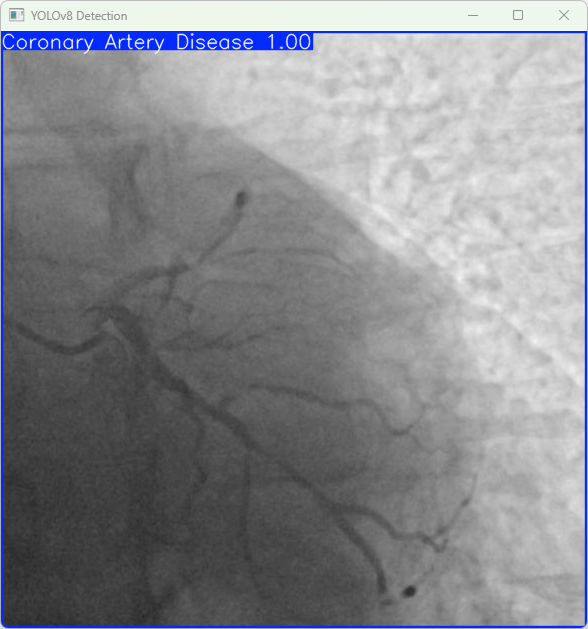

4.检测结果识别

模型训练完成后,我们可以得到一个最佳的训练结果模型best.pt文件,在runs/train/weights目录下。我们可以使用该文件进行后续的推理检测。

imgTest.py 图片检测代码如下:

检测图片:

(1)results = model(img_path):对指定的图片执行目标检测,results 包含检测结果。

显示检测结果:

(1)res = results[0].plot():将检测到的结果绘制在图片上。

(2)cv2.imshow(“YOLOv8 Detection”, res):使用OpenCV显示检测后的图片,窗口标题为“YOLOv8 Detection”。

(3)cv2.waitKey(0):等待用户按键关闭显示窗口

执行imgTest.py代码后,会将执行的结果直接标注在图片上,结果如下:

这段输出是基于YOLOv8模型对图片“imagetest.jpg”进行检测的结果,具体内容如下:

图像信息:

(1)处理的图像路径为:TestFiles/imagetest.jpg。

(2)图像尺寸为640×640像素。

检测结果:

(1)模型在图片中检测到:1 个冠状动脉疾病(Coronary Artery Disease)。

处理速度:

(1)预处理时间: 4.5 毫秒

(2)推理时间: 5.0 毫秒

(3)后处理时间: 81.1 毫秒

基于YOLOv8的冠状动脉疾病检测系统成功识别测试图像中的病灶区域,检测准确且运行速度较快,满足实时诊断需求。